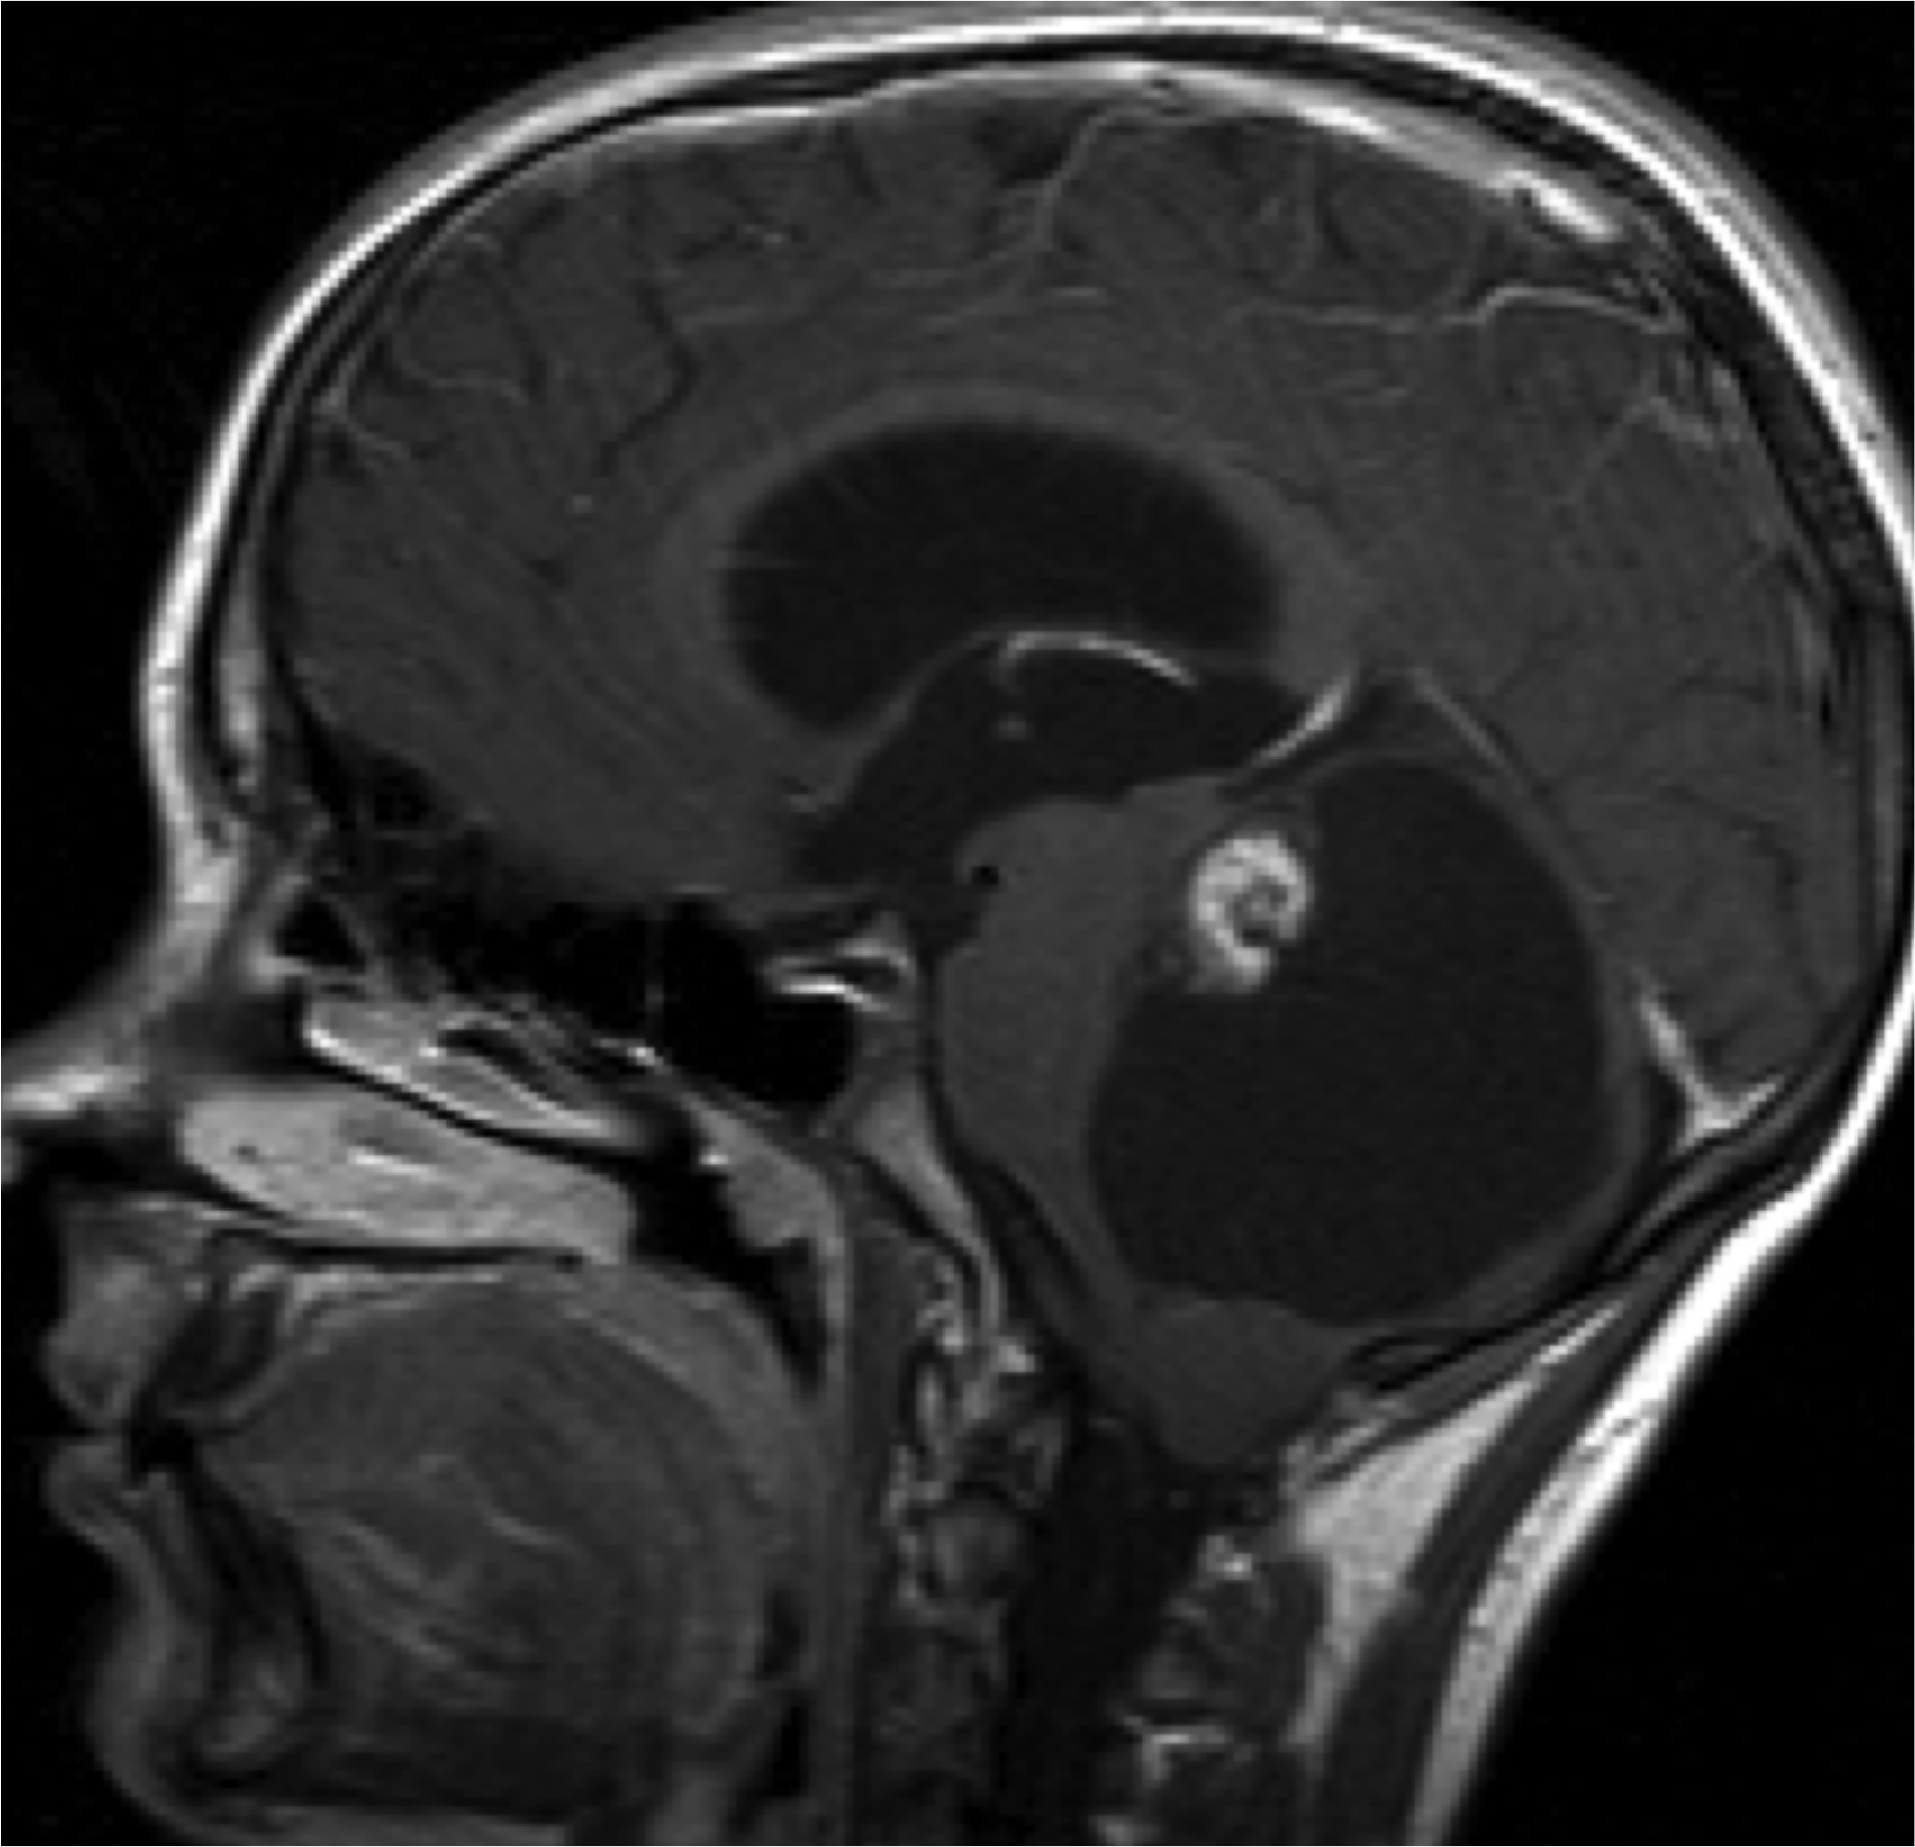

Amigdalar

- Por descenso de las amígdalas por el agujero magno.

- Lo normal es que las amígdalas cerebelosas (en imágenes sagitales)estén 5 mm por debajo del agujero magno en adultos y 7 mm en niños.